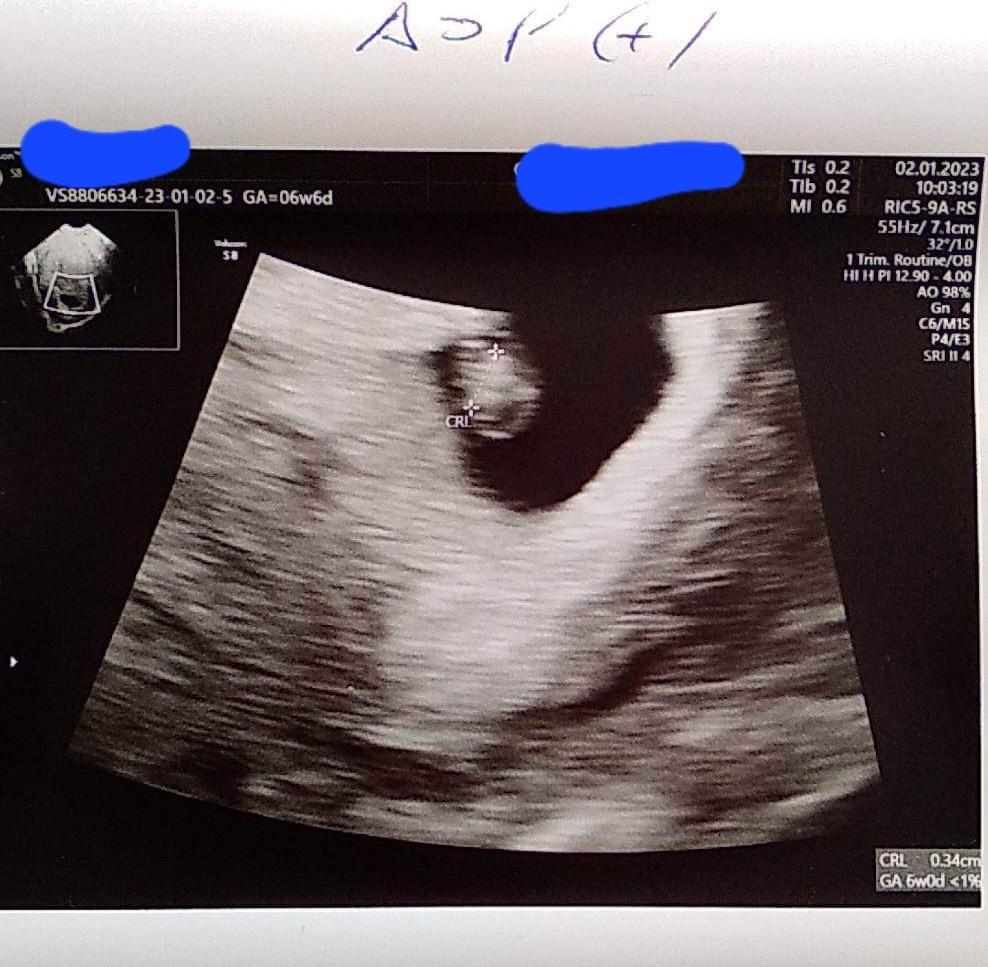

U nas 1.08 cm człowieczka, serduszko 128 ud/min - wg pani doktor na wiek ciąży jest ok. Wg OM jestem 7+2 i lekarka potwierdziła, że wg USG również także maluch rośnie w dobrym tempie